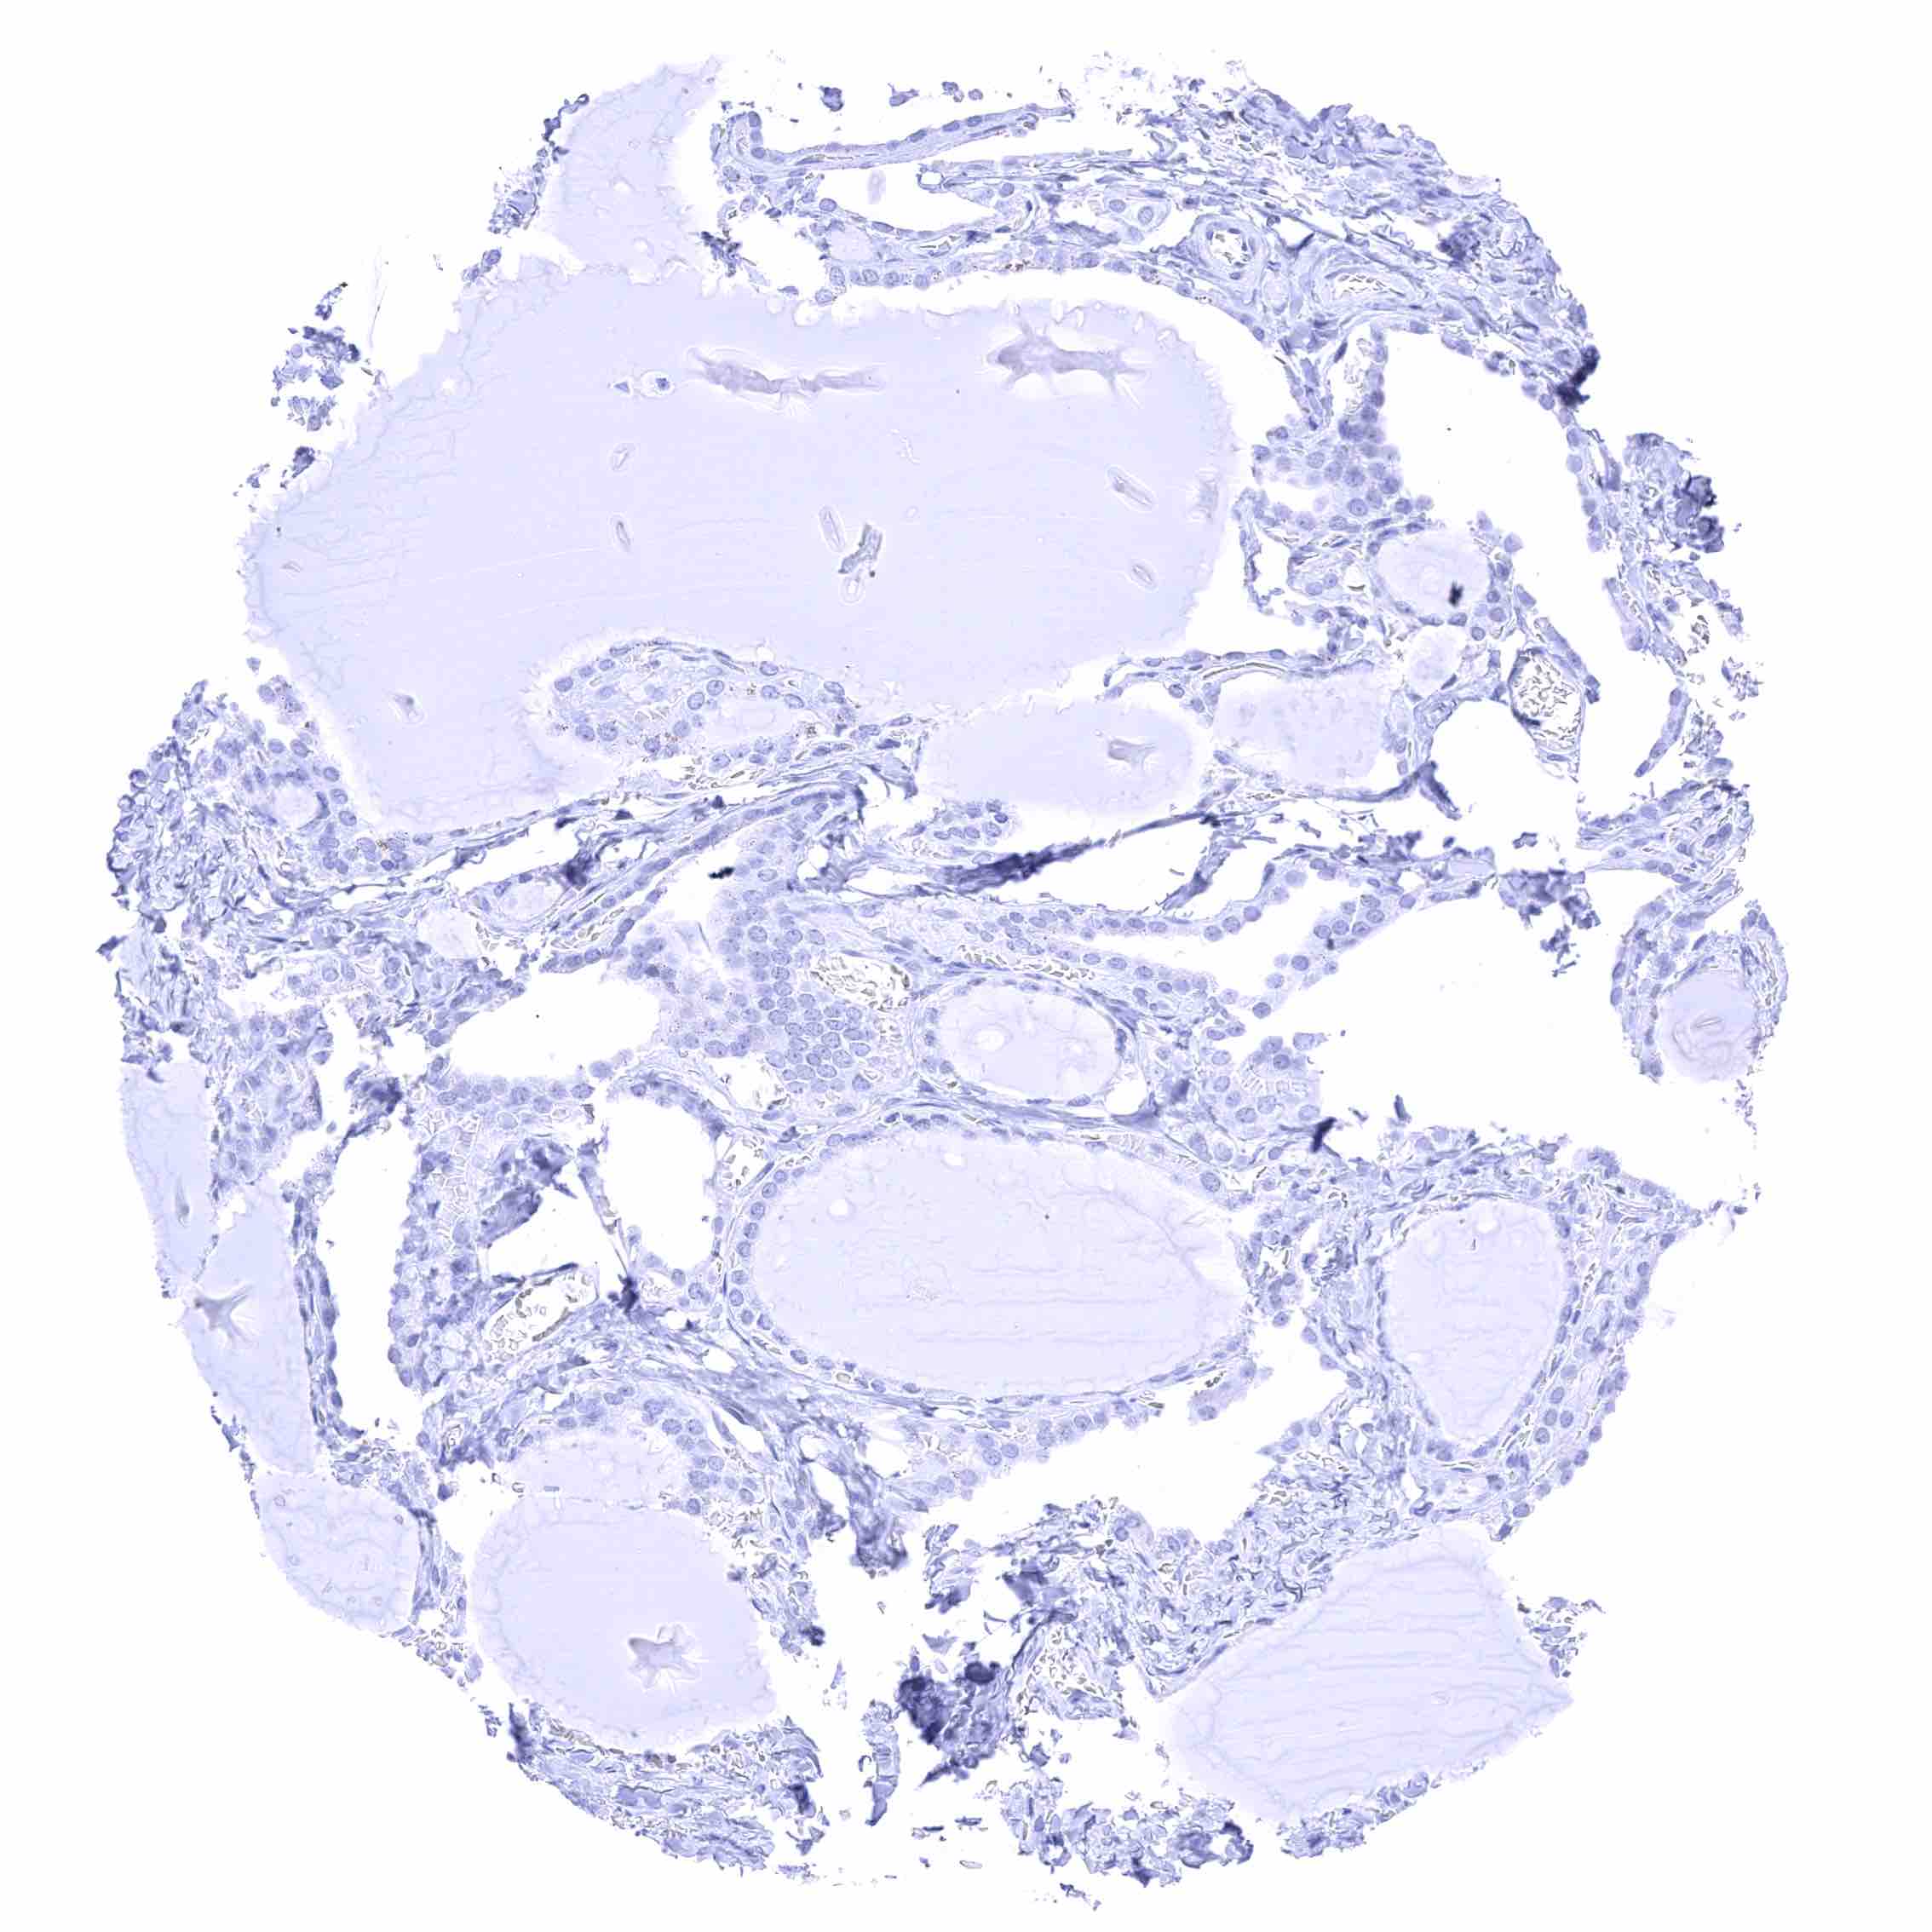

Thyroid gland